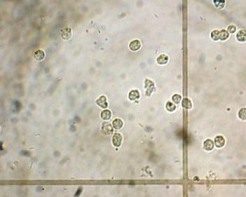

лейкоцитурия - лейкоциты в мочеВ норме, у здорового человека в моче может содержаться небольшое количество лейкоцитов: у мужчин от 0 до 3, у женщин от 0 до 6 в поле зрения. Данные нормы характерны для общего анализа мочи. В некоторых случаях для более точного подсчета количества лейкоцитов в моче, могут использоваться другие лабораторные методики (проба по Нечипоренко – в норме количество не превышает 4 тыс; проба Каковского-Адисса – норма не превышает 2 млн. в суточной моче).

Повышение количества лейкоцитов в моче (лейкоцитурия) – признак воспалительного процесса в мочеполовой системе, который может иметь как инфекционный (пиелонефрит, цистит, уретрит, простатит, везикулит, туберкулез почки…), так и неинфекционный характер (гломерулонефрит, интерстициальный нефрит…). Если на фоне повышенного количества Л. отсутствует бактериурия (бактерии в моче) – говорят о стерильной лейкоцитурии. Такая картина может быть связана либо с неинфекционными заболеваниями мочеполового тракта, либо имеет место бактериальный процесс, при котором возбудитель не выявляются при клиническом анализе мочи или стандартном бактериологическом исследовании (туберкулез мочеполовой системы, хламидиоз, микоплазмоз, уреаплазмоз).

В зависимости степени повышения количества Л. выделяют:

• незначительная лейкоцитурия – 8-40 в поле зрения

• умеренная Л. – 50-100 в поле зрения

• выраженная Л. – лейкоциты покрывают все поля зрения – пиурия (гной в моче).